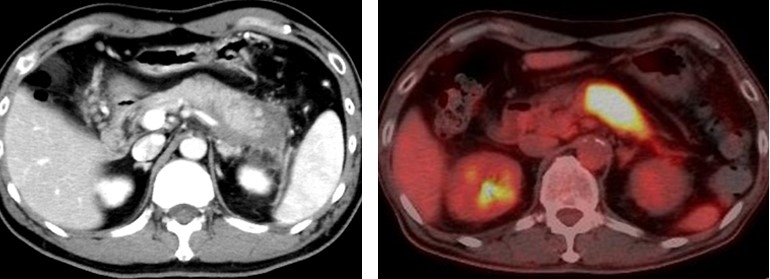

また、自己免疫性膵炎患者でも、ステロイド治療により病気の状態が改善すると、血清中のIL-22が大きく増加することも明らかになり、AhR活性化によるIL-22の増加が、自己免疫膵炎の発症抑制に寄与していることが明らかになりました。

本研究により、自己免疫性膵炎の発症メカニズムの解明や新規治療法の開発への新たな一歩に繋がることが期待されます。現在、近畿大学病院において、自己免疫性膵炎患者を対象として、青黛(試験薬名:青黛腸溶FC錠)を用いた臨床研究(試験ID:jRCTs051210171)を実施しており、青黛の安全性・有効性を確認する予定です。